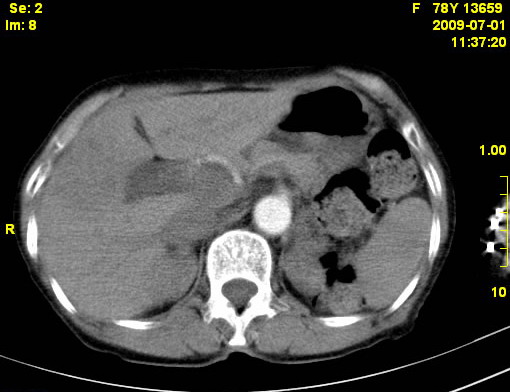

以下是引用zjzjr在2009-7-3 11:02:00的发言:[br]动脉期不均匀强化,门脉期及延迟期强化明显,肝门部见肿大淋巴结影,肝内胆管扩张.考虑肝右叶前段胆管细胞癌伴肝门淋巴结转移,胆内胆管扩张.慢性胆囊炎.

以下是引用dsl555在2009-7-4 10:59:00的发言:[br]考虑肝右叶前段胆管细胞癌伴肝门淋巴结转移,胆内胆管扩张.慢性胆囊炎. [br][br]支持。